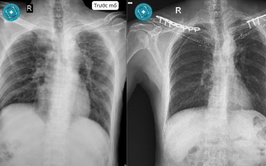

Nam bệnh nhân gãy cùng lúc hai xương đòn sau tai nạn giao thông

Tai nạn giao thông là nguyên nhân thường gặp của gãy xương đòn. Tuy nhiên, gãy đồng thời cả hai xương đòn ở cùng một bệnh nhân lại là tổn thương hiếm gặp.